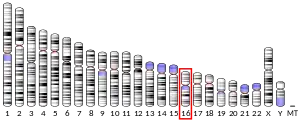

- ↑ Karin M, Eddy RL, Henry WM, Haley LL, Byers MG, Shows TB (Oct 1984). "Human metallothionein genes are clustered on chromosome 16". Proceedings of the National Academy of Sciences of the United States of America. 81 (17): 5494–8. Bibcode:1984PNAS...81.5494K. doi:10.1073/pnas.81.17.5494. PMC 391732. PMID 6089206.

- Le Beau MM, Diaz MO, Karin M, Rowley JD (1985). "Metallothionein gene cluster is split by chromosome 16 rearrangements in myelomonocytic leukaemia". Nature. 313 (6004): 709–11. Bibcode:1985Natur.313..709L. doi:10.1038/313709a0. PMID 3856101. S2CID 4321473.